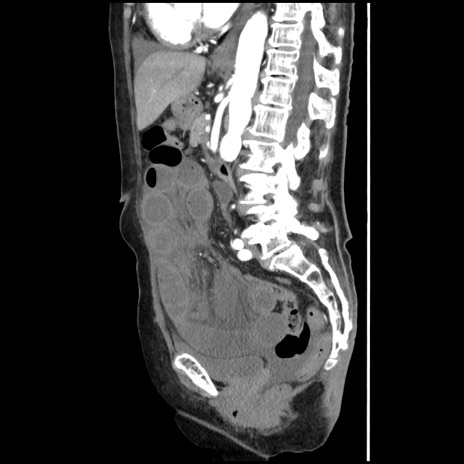

症例1(矢状断像)

【症例】80歳代女性

【主訴】腹痛

【現病歴】8時間前から腹痛あり来院。

【既往歴】糖尿病、脂質異常症、子宮体癌にて子宮全摘術

【身体所見】意識清明・会話良好だが腹痛で苦悶様、全腹部にわたって反跳痛と圧痛あり

【データ】WBC 13600、CRP 0.14、LDH 224、CK 90